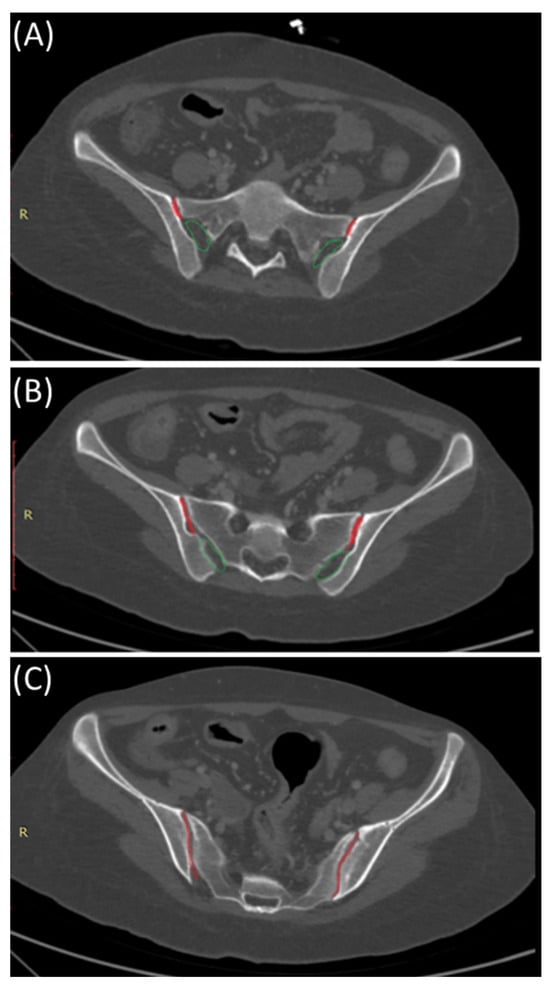

The SIJ is the largest axial joint in the body. It is often described as a C-shaped or an auricular-shaped structure [10,11]. As shown in Figure 2, the sacroiliac joint is divided into three parts craniocaudally. In the superior part, the posterior portion is syndesmotic up until the very superior section of the anterior part, where the interosseous sacroiliac ligament connects the sacrum and ilium and merges with the posterior sacroiliac ligament. In the middle part, the posterior section is syndesmotic, whereas the anterior part is synovial, and finally, the inferior part of the joint is identified as a true synovial joint [12,13,14]. These ligamentous connections alongside the muscles surrounding the SIJ limit the joint movement and provide stability [11,14]. There is a wide range of variability in the adult SIJ, including differences in shape and surface contour [14].

Figure 2.

Sacroiliac joint anatomy: Synovial and syndesmotic parts. Axial bone window CT images indicating the position of the synovial (red) and ligamentous (green) components of the sacroiliac joint from cranial (A), mid- (B), and caudal (C) parts of the sacroiliac joints.